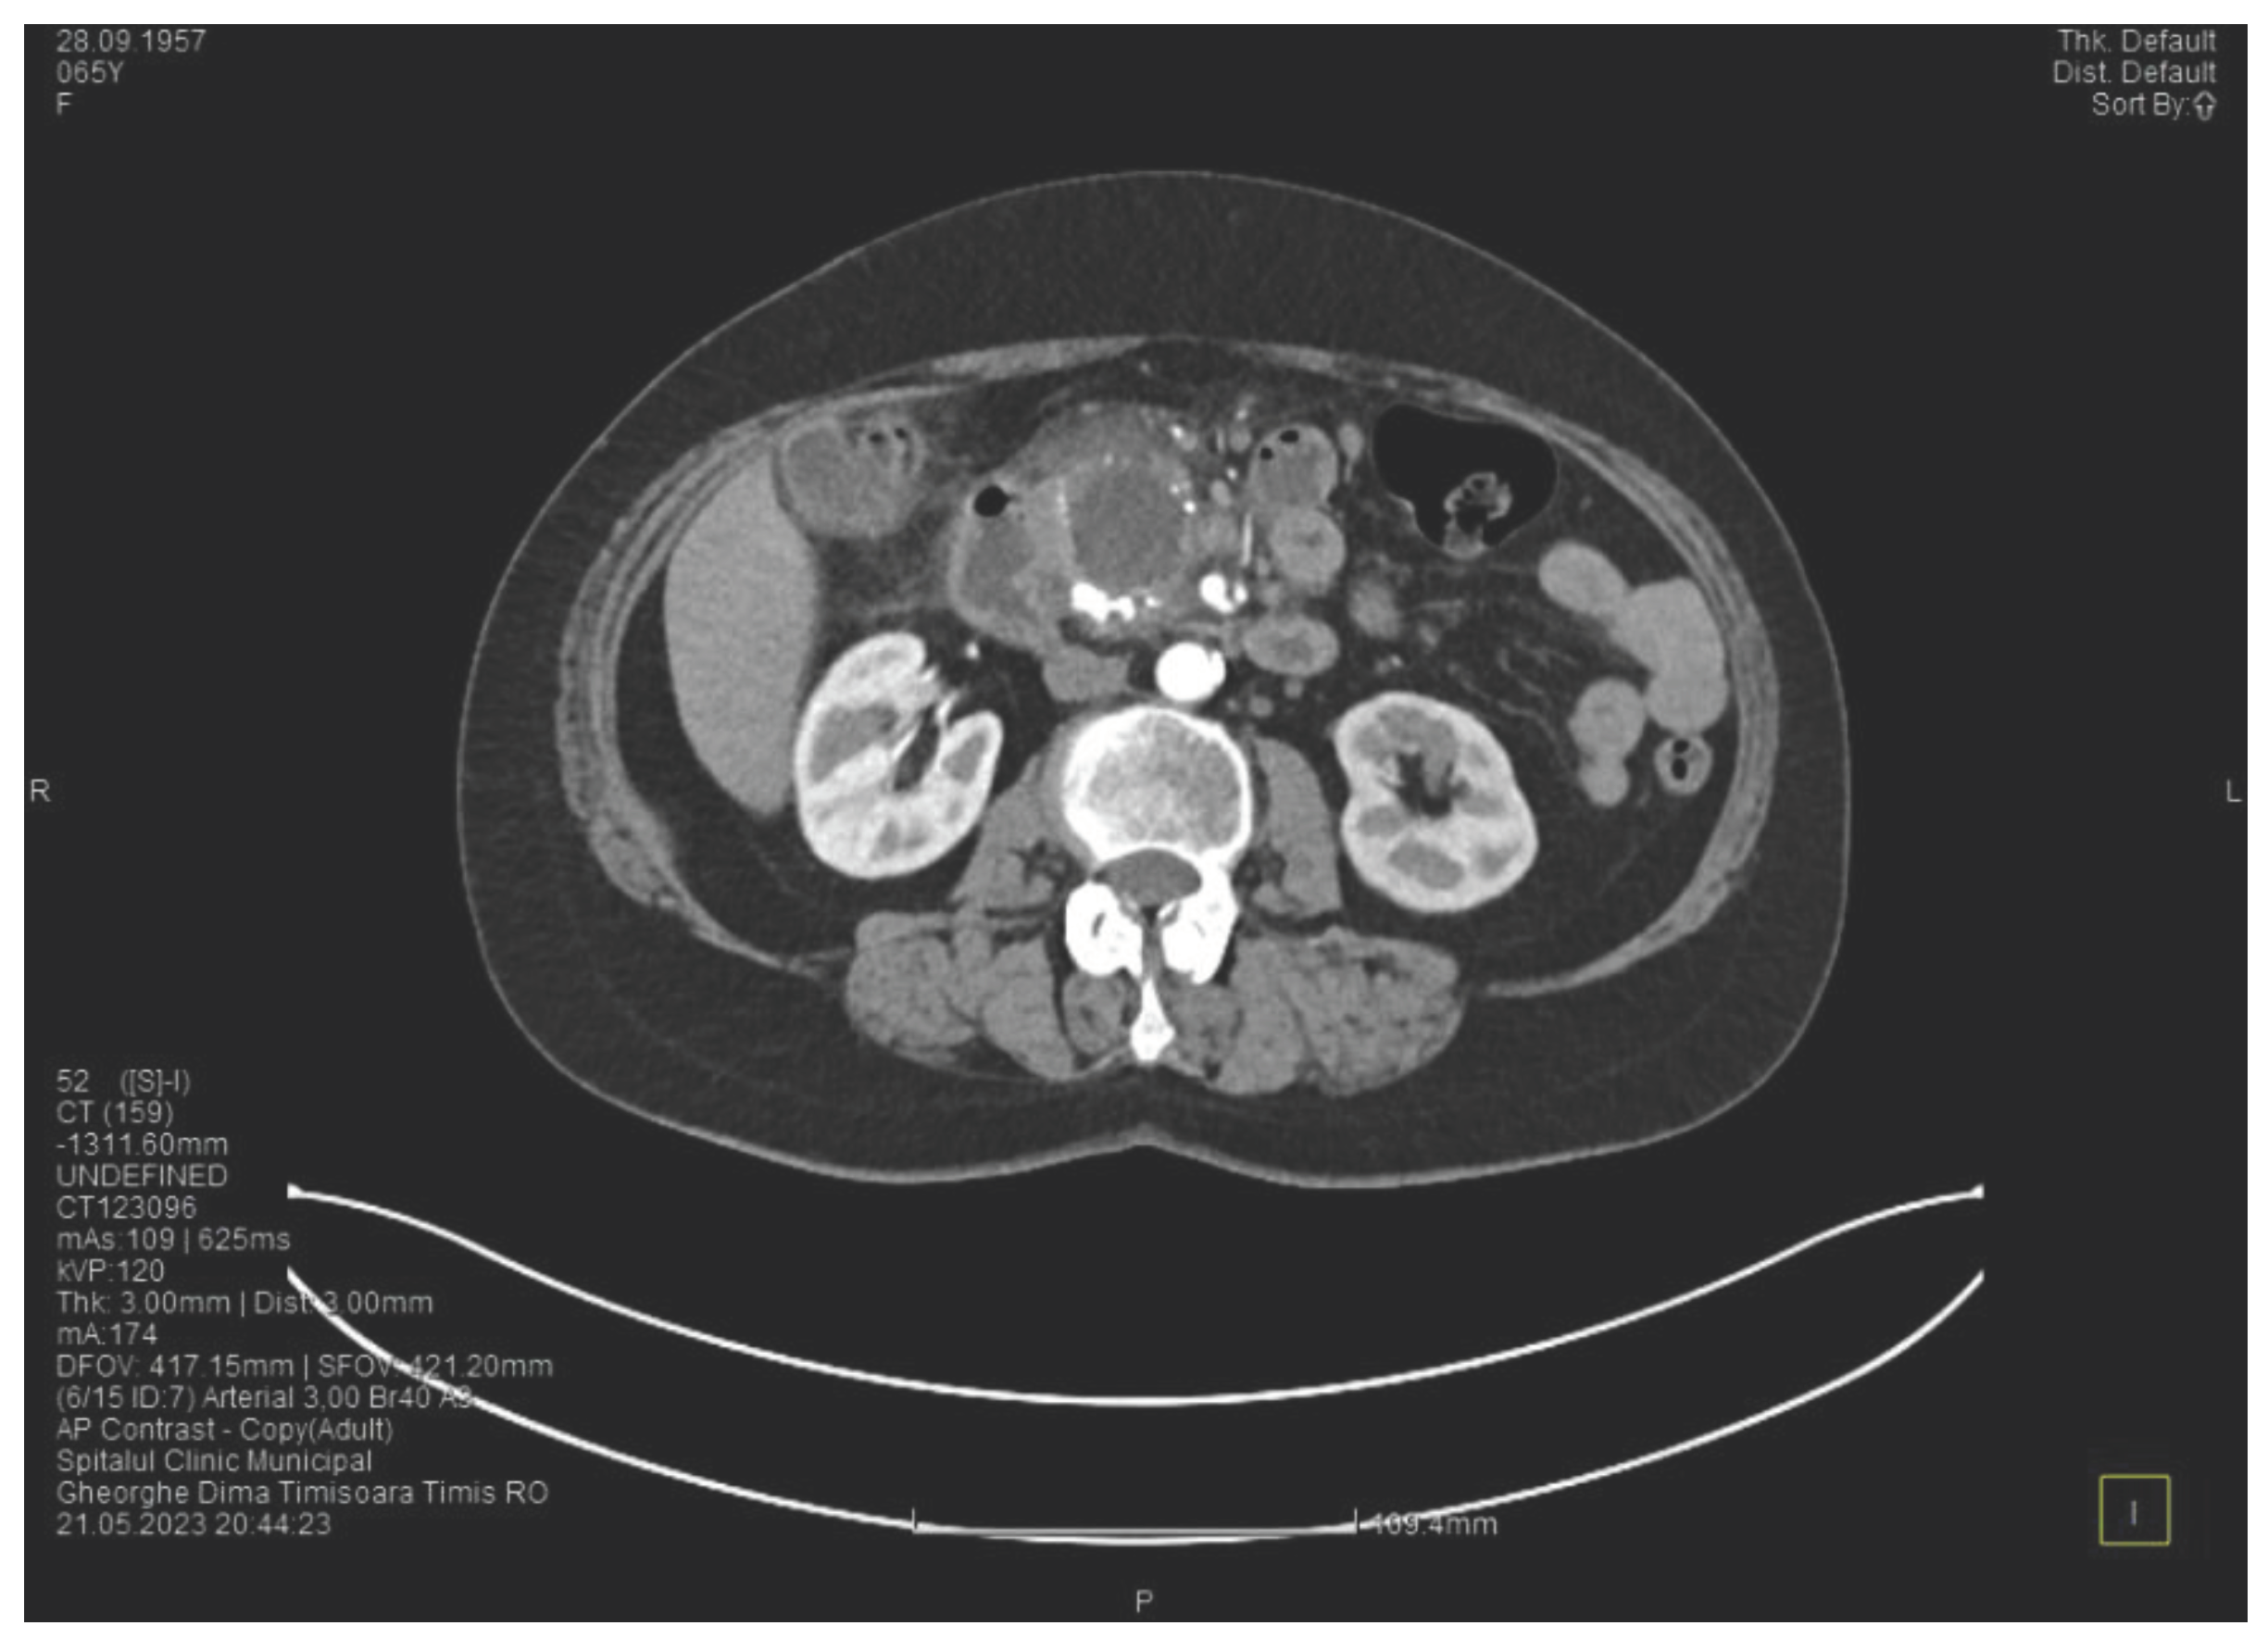

The contrast enhanced computed tomography showed changes suggestive for chronic pancreatitis, with multiple very small calcifications of the pancreatic tissue, a dilatation of the Wirsung duct in the corporeo-caudal area of approximately 15 mm (Figure 3) and a narrowing of the Wirsung tract in the cephalic area where calcareous conglomerates were present. In the anterior cephalo-uncinate area an oval cyst sized 31/28 mm is detected (larger than one month ago) (Figure 4). In the peri-cephalo-uncinate area we observed densifications of the adjacent fat extended towards the gastric antrum, the root of the mesentery and the hepatic flexure of the colon. There was a mild inflammatory enlargement of the peripancreatic lymph nodes and of the ons situated in the hepatic hilum. We also noticed a slight dilatation of the intrahepatic bile ducts and of the common hepatic duct and diffuse atheromatosis of the aorta, the iliac, and the common hepatic arteries. A gastroscopy is performed, which reveals normal esophagus, stomach and duodenal bulb.

Figure 4. The second CT scan shows a cyst in the pancreatic head and calcifications in the pancreatic head and in the groove area.